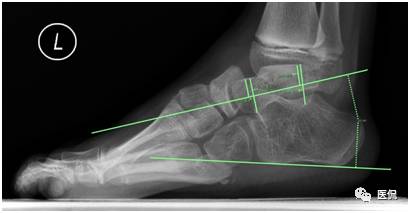

在提供的X线负重侧位图像上,关于角度的测量,下列正确的是(多选)

A 跟骨倾斜角的测量:跟骨下缘的连线、跟骨后结节低点与第五跖骨远端低点的连线,二者的夹角

B 跟骨中轴线的测量:与跟骨倾斜角的测量一致

C 距骨中轴线的测量:距骨距舟关节的中点与过滑车横断面的中点的连线

D 距骨中轴线的测量:距骨头低点与过滑车横断面低点的连线

E 第一跖骨中轴线的测量:第一跖骨近端与远端中点的连线

答案解读:A B E

解析:根据国外最新标准,在原有标准基础上略有修改,更能准确客观的进行数据的测量,测量如下(以左足为例):如下图。

测量数据说明:测量的数据可反映病理改变及其程度,用以下角度加以说明。一是跟距角明显变小(正常值25-45度),严重者跟骨与距骨接近平行;二是跟骨倾斜角变小(正常值17-32度);三是距骨与第一跖骨向上成角,且大于4度。关于角度的测量,中轴线的定位尤为重要,不准确也会影响最终诊断。根据国外最新标准在原有标准基础上略有修改,更能准确客观的进行数据的测量,测量方法见后文。